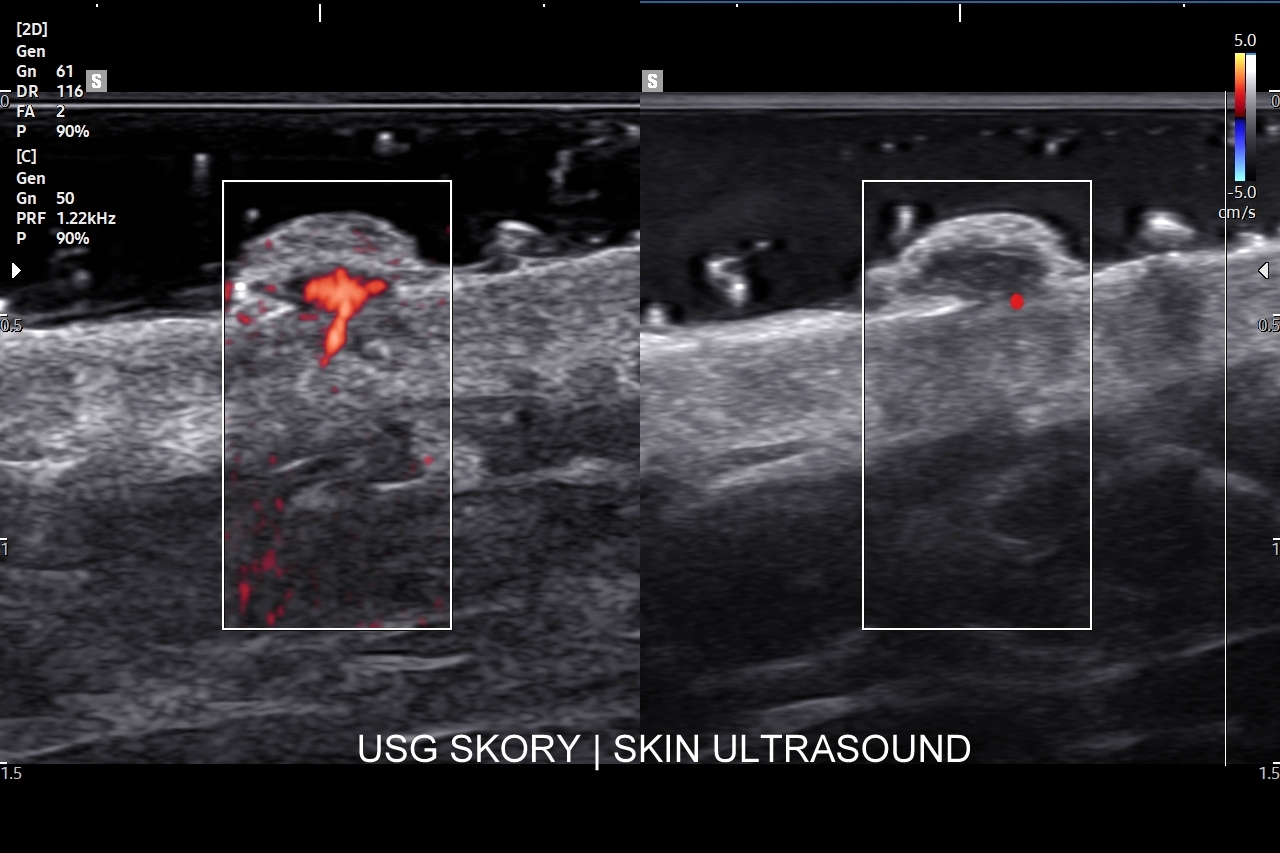

Badanie USG skóry i powłok jest metodą diagnostyczną, która swoją czułością oraz dokładnością przewyższa w ocenie patologii powłok badanie rezonansem magnetycznym. W obrębie powłok ciała w badaniu USG najczęściej rozpoznaje się różnorodne guzy oraz stany zapalne. Wśród guzów dominują łagodne tłuszczaki, kaszaki i torbiele inkluzyjne, a także przepukliny. U młodszych pacjentów często wykrywa się naczyniaki. Rzadziej spotkane są guzy złośliwe jak mięsaki, czy przerzuty nowotworowe. W pracowni USG dr Szczepańskiego poza wizualną oceną guzów powłok przeprowadzana jest ich ocena biologii w kontekście cech złośliwości i oceny przewidywalnego tempa wzrostu.

W obrębie schorzeń zapalnych typowo wykrywa się ropnie, przetoki, infekcyjne zapalenia tkanki podskórnej (np. róża), rzadziej głębsze infekcje powięzi i zagrażające życiu infekcje podpowięziowe. Badanie USG powłok jest bardzo przydatne w chirurgii, gdyż dzięki niemu można szybko i sprawnie zdiagnozować powikłania chirurgiczne takie jak krwiaki, zacieki, ropnie, ciała obce, przepukliny brzuszne, a także można oceniać i monitorować gojenie się blizny, czy położenie drenów. USG pomaga także diagnozować endometriozę w powłokach brzucha i w bliznach po cięciu cesarskim.

Badanie USG twarzy, często nie do końca fortunnie zwane USG skóry twarzy, to stosunkowo nowa metoda diagnostyczna wprowadzona we Wrocławiu do użytku przez dr Tomasza Szczepańskiego, a wykonywana w przypadku schorzeń z zakresu medycyny estetycznej, dermatologii, laryngologii, stomatologii i chirurgii. Wśród rozpoznań w badaniu USG skóry twarzy dominują choroby infekcyjne takie jak rozprzestrzeniające się w tkankach miękkich zapalenia i ropowice pochodzące od zapaleń zębów czy migdałków, powikłania ropne w przebiegu trądziku pospolitego lub różowatego, po iniekcjach wypełniaczy i po innych zabiegach z zakresu medycyny estetycznej. Kolejną dużą grupą patologii skóry twarzy są torbiele inkluzyjne, których przykładem są kaszaki, oraz guzy twarzy, wśród których dominują ziarniniaki jako odległe acz częste powikłanie depozycji wypełniaczy z kwasu hialuronowego.